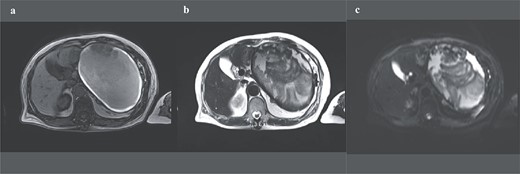

A 74-year-old Asian woman had been treated for diabetes mellitus but had stopped treatment on her own. The HbA1c level increased sharply to 16%. Blood samples showed no abnormal findings such as elevated levels of tumor markers (Table 1). There was no history of abdominal imaging, sudden abdominal pain, abdominal trauma, or abdominal surgery. Contrast-enhanced abdominal computed tomography (CT) revealed a large hematoma-like cystic lesion in the pancreatic tail (Fig. 1a–c). Calcification of the wall and internal septum was prominent. Magnetic resonance imaging (MRI) demonstrated a 156 × 112 mm marginal T1W high signal (Fig. 2a) and an internal T2W uneven low signal (Fig. 2b) on the dorsal side of the stomach, suggesting a hematoma-like cystic lesion. Diffusion showed a high signal intensity, but abnormal enhancement was not observed (Fig. 2c). Considering the possibility of intra-abdominal dissemination of the cystic tumor via a puncture, the patient underwent distal pancreatectomy and splenectomy with lymph node dissection for diagnostic and therapeutic purposes. The cyst wall adhered strongly to the surrounding tissue (Fig. 3); however, no adverse events were noted during the operation. The operating time was 7 h 19 min, and blood loss was 809 ml. The patient was discharged 11 days postoperatively, with a good postoperative course.

Preoperative abdominal enhanced CT showing a large hematoma-like cystic lesion in the pancreatic tail.